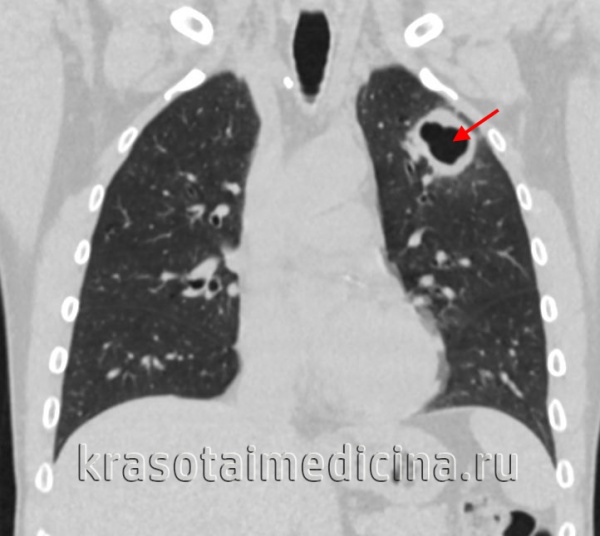

• инфильтративный (45,5%, п=10);

• диссеминированный (22,7%, п=5);

• милиарный (9,1%, п=2);

• у 5 пациентов был выявлен плеврит (22,7%).

Микобактерии туберкулеза были выявлены методом бактериоскопии у трех пациентов — они были переведены в специализированный противотуберкулезный стационар; 19 пациентов после выписки направлены на дальнейшее дообследование и лечение в противотуберкулезный диспансер (ПТД) по месту жительства.